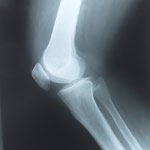

על שיכוך כאבים באורתופדיה

על דלקת מפרקים שגרונית

לא על רגל אחת: שבר בכף רגל וקרסול

כואב לכם הגב?

אורתופדיה: על הכתפיים

שינויים ניווניים בכתף